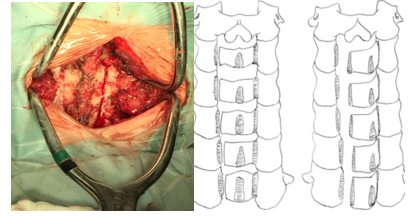

Figura 1: Procedimiento quirúrgico: disección, osteotomías y estabilización con mini placas, tornillos lamino articulares

Se realiza la osteotomía completa con fresa a nivel de la unión de las láminas con los macizos articulares del lado a abrir, Una vez realizada la osteotomía se procede al lado contralateral, realizando una osteotomía incompleta con fresa, logrando una bisagra con cierta capacidad de ceder. Se completa la osteotomía con Kerrison de 1 o 2 mm. Se realizó la osteotomía del lado que presentaba elementos radiculares, de no tenerlos quedaba a criterio del cirujano (a izquierda) Figura 2.

Figura 4: Esquema sobre la técnica deO'Brien et al.para laminoplastia cervical expansiva. A. Tiempo óseo con corte de las láminas. B. Apertura lateral (open door). C. Estabilización con miniplacas